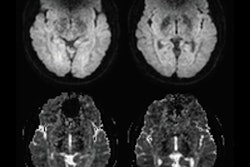

For this retrospective study, Tanaka and colleagues searched records at two Mayo Clinic facilities between January 2012 and June 2016 and found 25 patients who met the inclusion criteria. The team examined 28 prostate scans taken on 1.5-tesla MRI systems (Optima MR450w or Signa HDxt, GE Healthcare) with an endorectal coil and pelvic phased-array coil. All subjects had either an implanted pacemaker or ICD and were matched with patients with no CIEDs, who served as a control group (AJR, April 2019, Vol. 212:4, pp. 815-822).

The study also included two independent readers who rated image quality and artifacts on a five-point scale based on T2-weighted, diffusion-weighted, and dynamic contrast-enhanced images.

As for image quality, the team found no statistically significant difference between the two readers based on regional anatomy, artifacts, and overall imaging preferences in either the CIED group or control subjects. Their lack of differentiation also held true for the three MR imaging sequences individually and when combined.